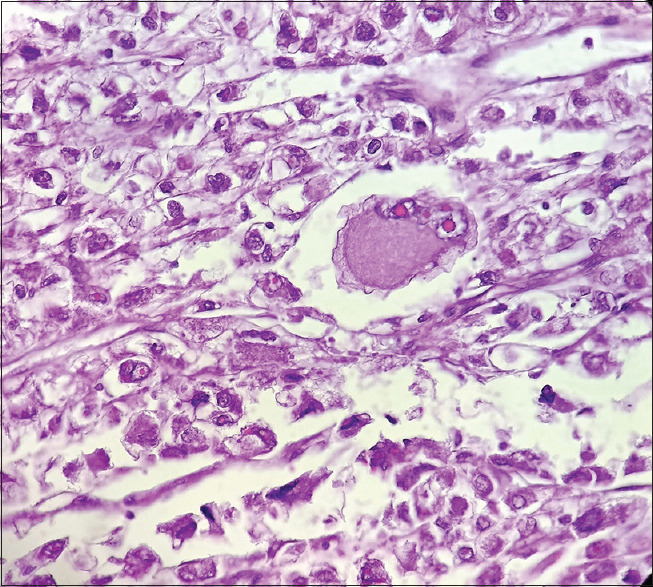

血管周围上皮样细胞瘤(PEComas)具有独特的形态,由血管周围上皮细胞组成,表达黑色素细胞和平滑肌细胞标记物。妇科PEComas约占所有PEComas的25%,在大多数情况下,肿瘤的原发部位是子宫体。卵巢PEComa是例外。在此,我们报告一例38岁女性原发性卵巢恶性PEComa。

Perivascular epithelioid cell tumors (PEComas) have unique morphology comprised perivascular epitheloid cells and express both melanocytic and smooth muscle cell markers. Gynecological PEComas account for approximately 25% of all PEComas, and in most cases, the primary site of the tumor is the uterine body. Ovarian PEComa is exceptional. Here, we report a case of primary malignant PEComa of ovary in a 38 years female.